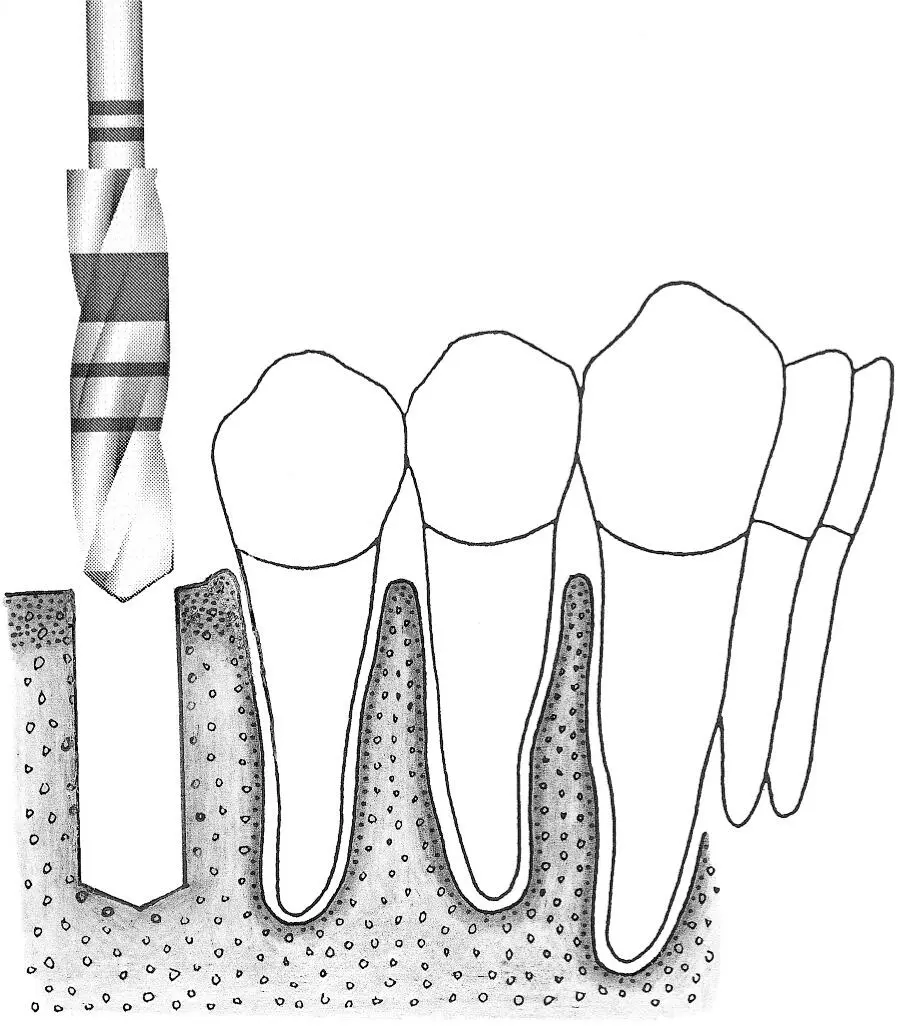

Fig 1-2Sequence of site preparation for a standard implant.

Fig 1-2i Occasionally, when the bone structure is uniformly dense, bone tapping is performed prior to implant placement.

Fig 1-2j A standard implant is placed in the site, with the rough surface positioned at the level of the alveolar ridge crest. This allows the implant shoulder to be located at the gingival level.